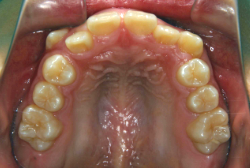

診断の結果、典型的なアングル2級1類の上顎前突です。上下歯列の正中の不一致も見られます。しかし、歯の大きさは平均値に近く、配列の凸凹がそれほど見られません。このまま放置すると、将来的には抜歯を伴う矯正治療を行う可能性が高くなりますが、このタイミングで適切な治療をすると、非抜歯治療が可能かもしれません。

矯正歯科医が着目するのは、奥歯の噛み合わせの位置関係です。前歯の位置にそれなりの差が生じていても、奥歯の位置が正しければそれほど重症という評価にはなりません。このケースの場合は、上下の第一大臼歯の位置関係は、直線的に一致しているタイプでした(矢印が一致)。混合歯列時期の奥歯の位置関係としては、ほぼ正常な状態といえますが、症状から言うと、上の奥歯をもっと後ろに下げてやることができれば、上顎歯列全体に余裕ができるので、凸凹も解消できるし、前歯の傾きを内向きに修正することもできると考えられました。しかしこのまま全体に永久歯が生えきってしまうと、上の前歯が出たままになってしまいますので、生え替わりが完了する前に大急ぎで奥歯を後ろに下げる必要があると判断しました。

こういう症状でもっとも効果があるのが、顎外固定装置と言って、お口の外部から奥歯に力をかける方法です。 写真の装置はネックバンドというタイプの装置です。この装置は取り外し式ですので、夜寝るときに毎日自分で取り付けて、寝ている間に少しずつ上の奥歯を後ろに下げていきます。この装置には、奥歯を後ろに下げる効果だけでなく、上顎の過剰な成長発育の抑制、下顎の成長促進作用があるとされており、上顎前突の症状にはいずれも有利な効果が期待できます。

ネックバンドを1年半使用して、上顎大臼歯が十分後ろに下がったところで、裏側にリンガルアーチという固定のワイヤーを取り付けて、新しく生じた隙間が狭くならないよう「保隙(ほげき)」という処置をして、永久歯が生えそろうまで待機中の様子です。配列全体に隙間が生じているのがお分かりいただけると思います。これだけの隙間が確保できていれば、抜歯をしなくても、あとで上の前歯を内側に理想的な角度で引っ込めることができます。このように完全に永久歯列になる前に、十分な隙間が確保できるかどうかが、非抜歯で矯正できるかどうかの分かれ目になります。